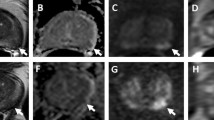

(a–e) PI-RADS 4 lesion in the peripheral zone. (a) Axial and (b) coronal T2-weighted sequence showing moderate diffuse (non-circumscribed) hypointensity of the bilateral peripheral zone (PI-RADS score 3). (c) Diffusion weighted high b-value (calculated b = 1400 s/mm2) image shows mildly hyperintense signal intensity in the right anterior and lateral peripheral zone (PI-RADS score 3). (d) ADC map correspondingly shows moderate hypointense signal intensity (dominant sequence for the peripheral zone) in the right anterior and lateral peripheral zone (PI-RADS score 3). (e) DCE sequence shows focal and contemporary enhancement (DCE positive) consistent with an upgrading to an overall PI-RADS score of 4. MRI/US fusion guided biopsy revealed a Gleason 3 + 4 = 7 adenocarcinoma (PSA level 6.9 ng/mL). (Reproduced from. https://doi.org/10.1007/978-3-319-75019-4_11)